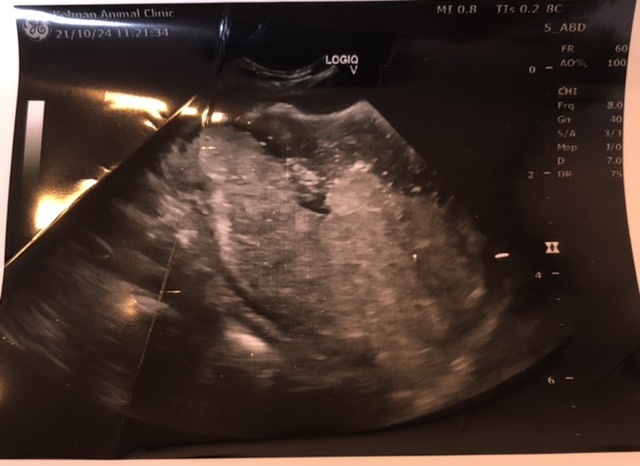

しかしながら、10月中旬から食欲不振が続き嘔吐を繰り返すようになったため近所の病院へ行くと、超音波検査の結果胃幽門部に腫瘍病変を疑う肥厚を認めるとのことから大きな病院で内視鏡化での生検、CT画像での腫瘍の範囲を決定するよう勧められ別の病院を紹介されることになりました。

この後、紹介いただいた病院で再度、血液検査、エコー検査を受けると間違いなく腫瘍が確認されるとのことからCT検査および内視鏡検査(腫瘍部生検)を受ける予約を1週間後にお願いいたしました。

①CT検査にて胃の幽門部にかけ複数のポリープが確認されました。

(上記にエコー写真およびCT画像を掲載しております)